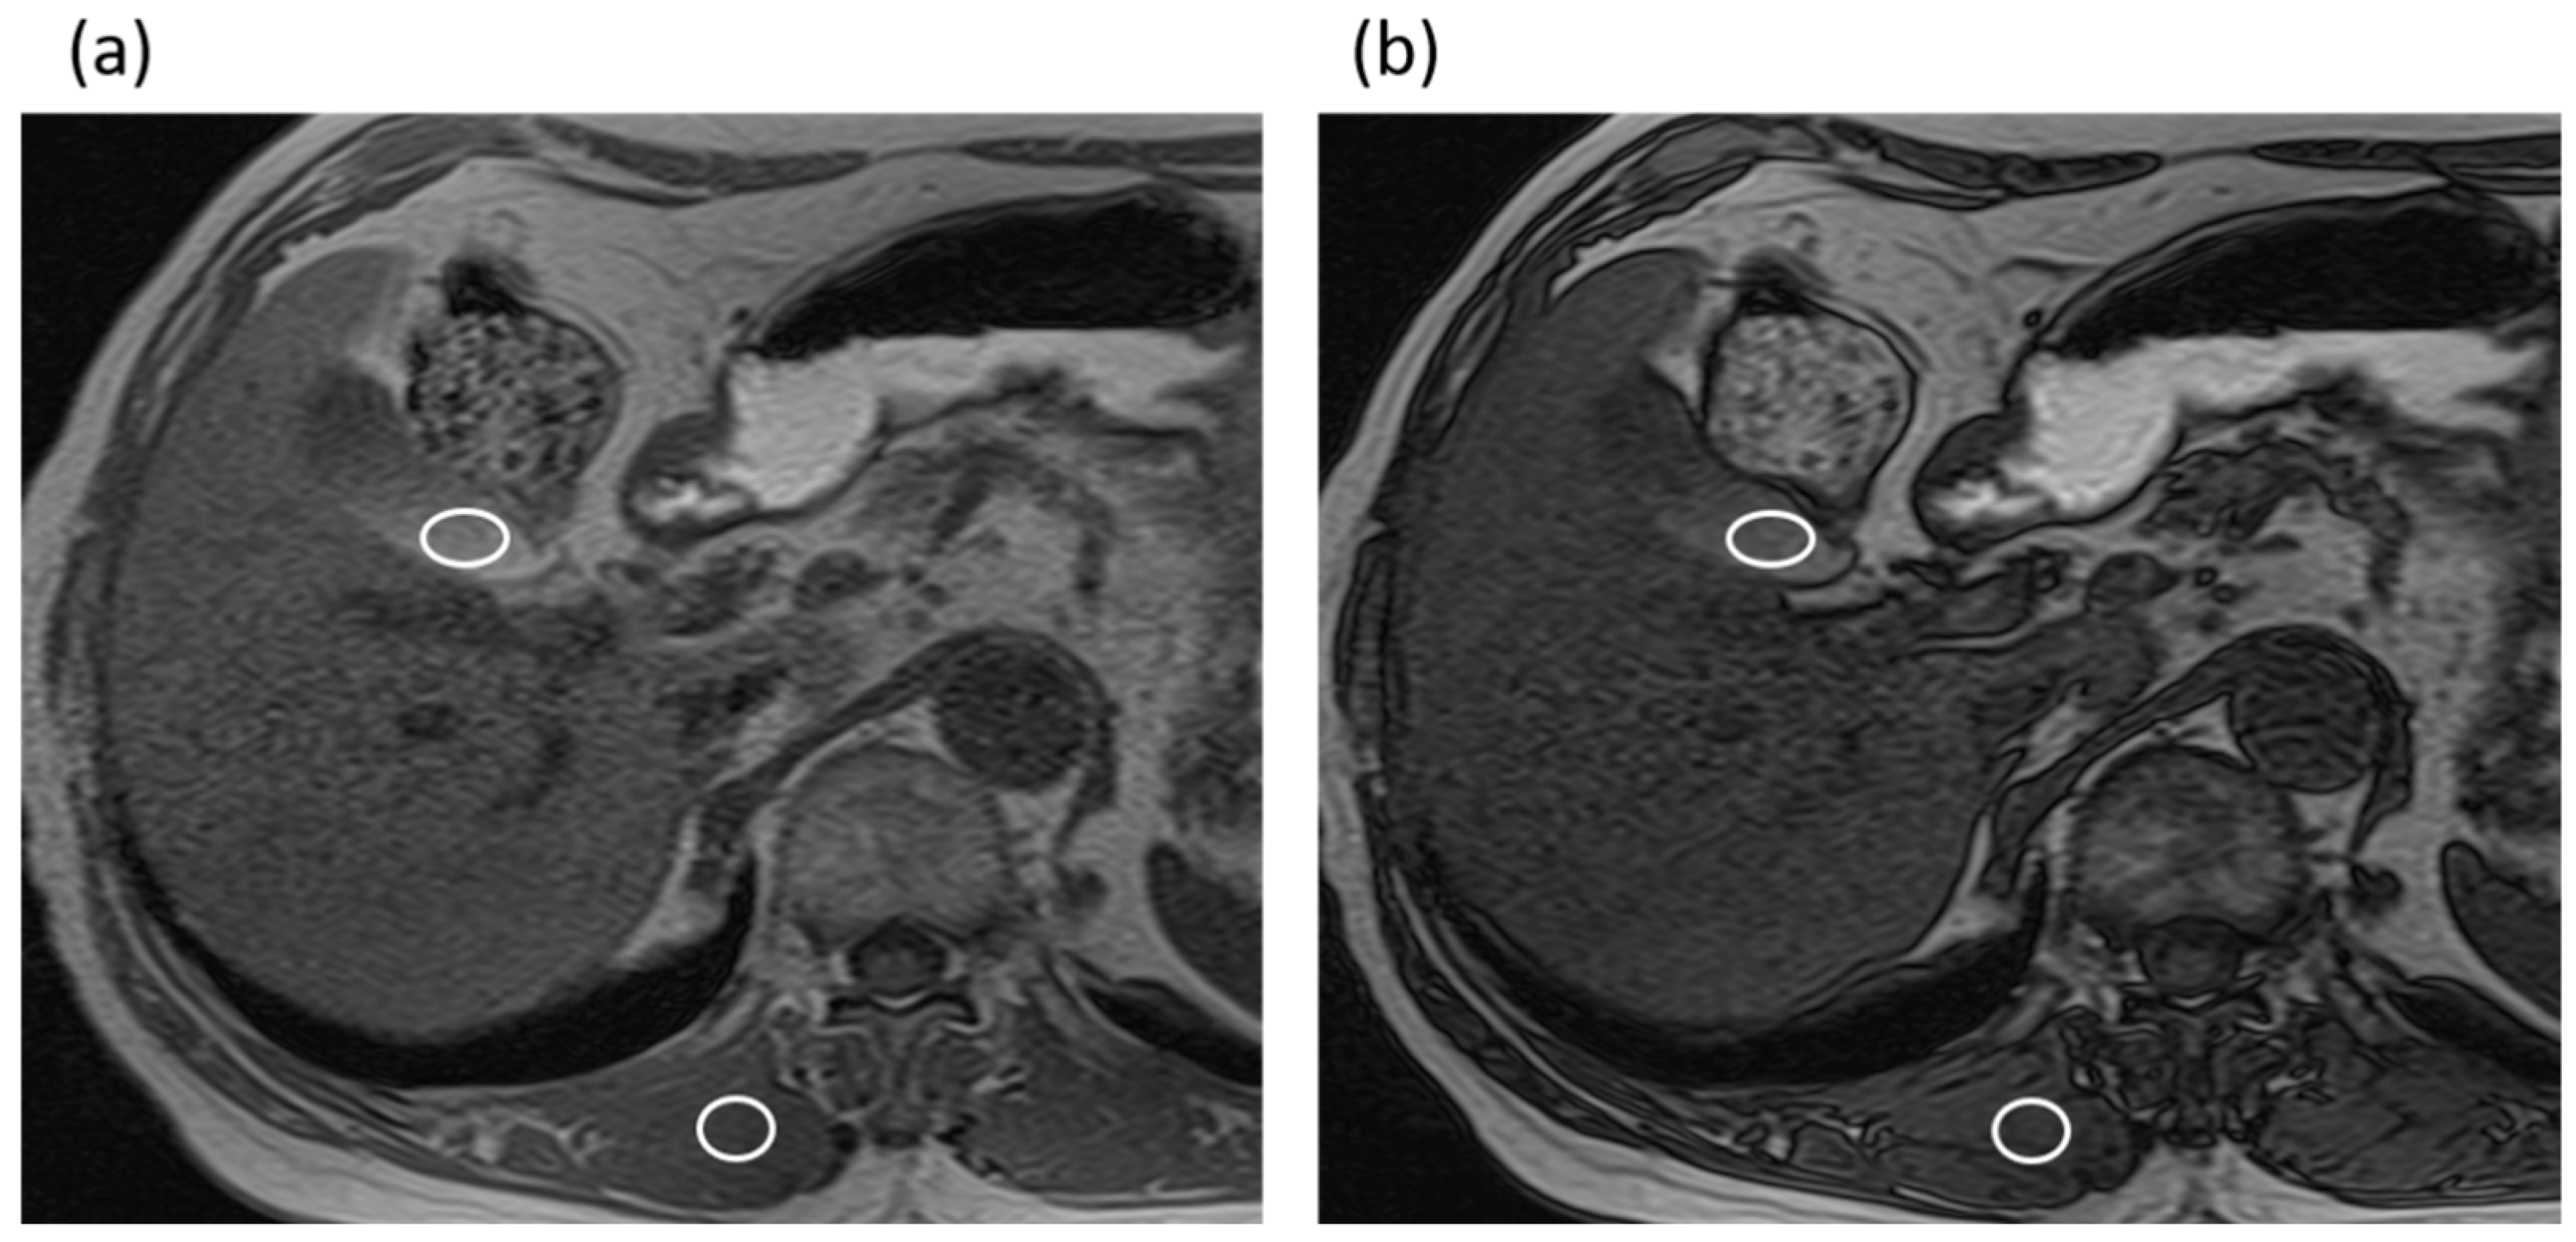

The three radiologists measured the maximal diameter of the common bile duct perpendicularly to the long axis of the duct on MRCP images without the IR pulse by using an electronic caliper. The averaged common duct diameter of the two radiologists’ measurements was used for the data analysis. In addition, the three radiologists also measured the signal intensities (SIs) of the gallbladder (SIgallbladder) and paraspinal muscle (SImuscle) on the T1-weighted gradient-echo in-phase and opposed-phase images using operator-defined regions of interest (ROIs), in consensus. The signal intensity of gallbladder is often heterogeneous, forming gradational layering. Therefore, an effort was made to draw the ROI circles as large as possible in a high-signal area of the gallbladder on the in-phase images while avoiding the gallstones and artifacts, and the ROI was then copied and pasted on the opposed-phase images (Figure 2). The SI ratio (SIR) was then calculated from the SIgallbladder and the SImuscle as SIgallbladder/SImuscle in each image. In addition, the signal reduction ratio (SRR) was calculated as follows: SRR = [(SIR in-phase) − (SIR opposed-phase)]/(SIR in-phase).

Figure 2.

An 82-year-old man with intraductal papillary mucinous neoplasm in the non-gallstone group. (a) T1-weighted gradient-echo in-phase image. The gallbladder-to-muscle SIR was 2.12. (b) T1-weighted gradient-echo opposed-phase image. The gallbladder-to-muscle SIR was 1.72. The SRR of the gallbladder was 0.19.